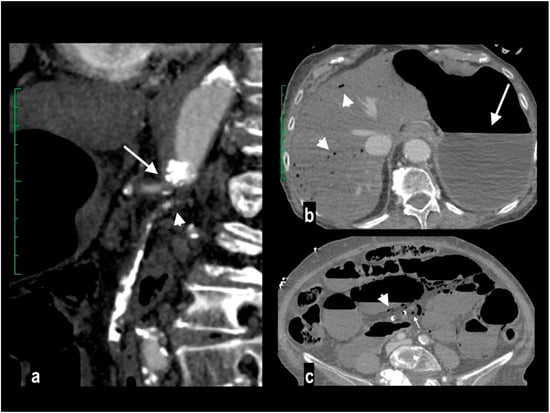

Figure 4.

A 78-year-old woman with massive mesenteric ischemia. Atherosclerotic occlusion of the origin of the celiac trunk (arrow) and the proximal SMA (arrowhead) (a). Intrahepatic pneumatosis (arrowheads) and gastrectasia (arrow) (b). Hypoenhancing dilated paper-thin bowel wall with parietal pneumatosis (arrowheads) and mesenteric venous pneumatosis (arrow) were reported (c). The patient died a few hours after emergency room access.

Atherosclerotic steno-occlusion is usually observed in older patients with a history of systemic vasculopathy, and the risk of AMI increases when a critical stenosis involves two of the three major visceral arteries (Figure 4).